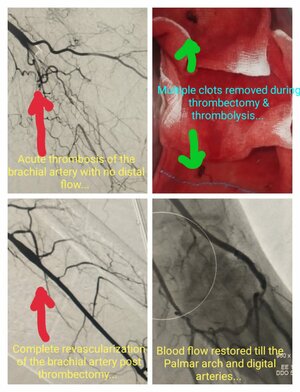

Brachial Artery Thrombectomy